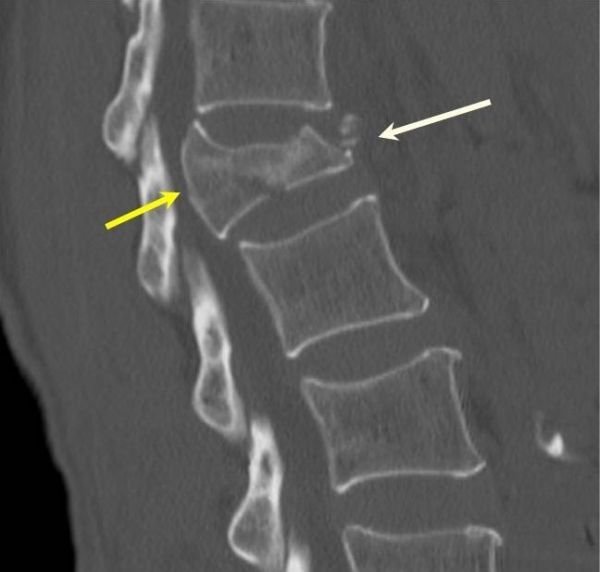

Essa fratura geralmente é causada por traumatismo mais significativo (por exemplo, acidente de carro). Ela acontece quando a vértebra é esmagada por forças axiais. Em uma fratura explosão, a vértebra é fraturada em vários lugares (pelo menos 2 colunas das 3 colunas de Denis – veja explicação abaixo). Em alguns casos, fragmentos ósseos podem comprimir o canal vertebral onde está a medula espinhal e raízes nervosas. Esse tipo de fratura gera maior instabilidade.

A tomografia permite um maior detalhamento dessas estruturas ósseas e pode ser solicitada na dúvida diagnóstica, na avaliação de estabilidade ou no acompanhamento do tratamento.

Já a ressonância magnética, permite melhor visualização de estruturas neurológicas, ligamentares e discais. A ressonância também auxilia na diferenciação entre fraturas agudas e crônicas.